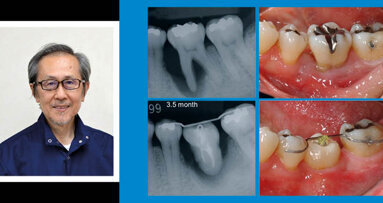

През ноември 2018 г. в България ще гостува светилото в областта на ...